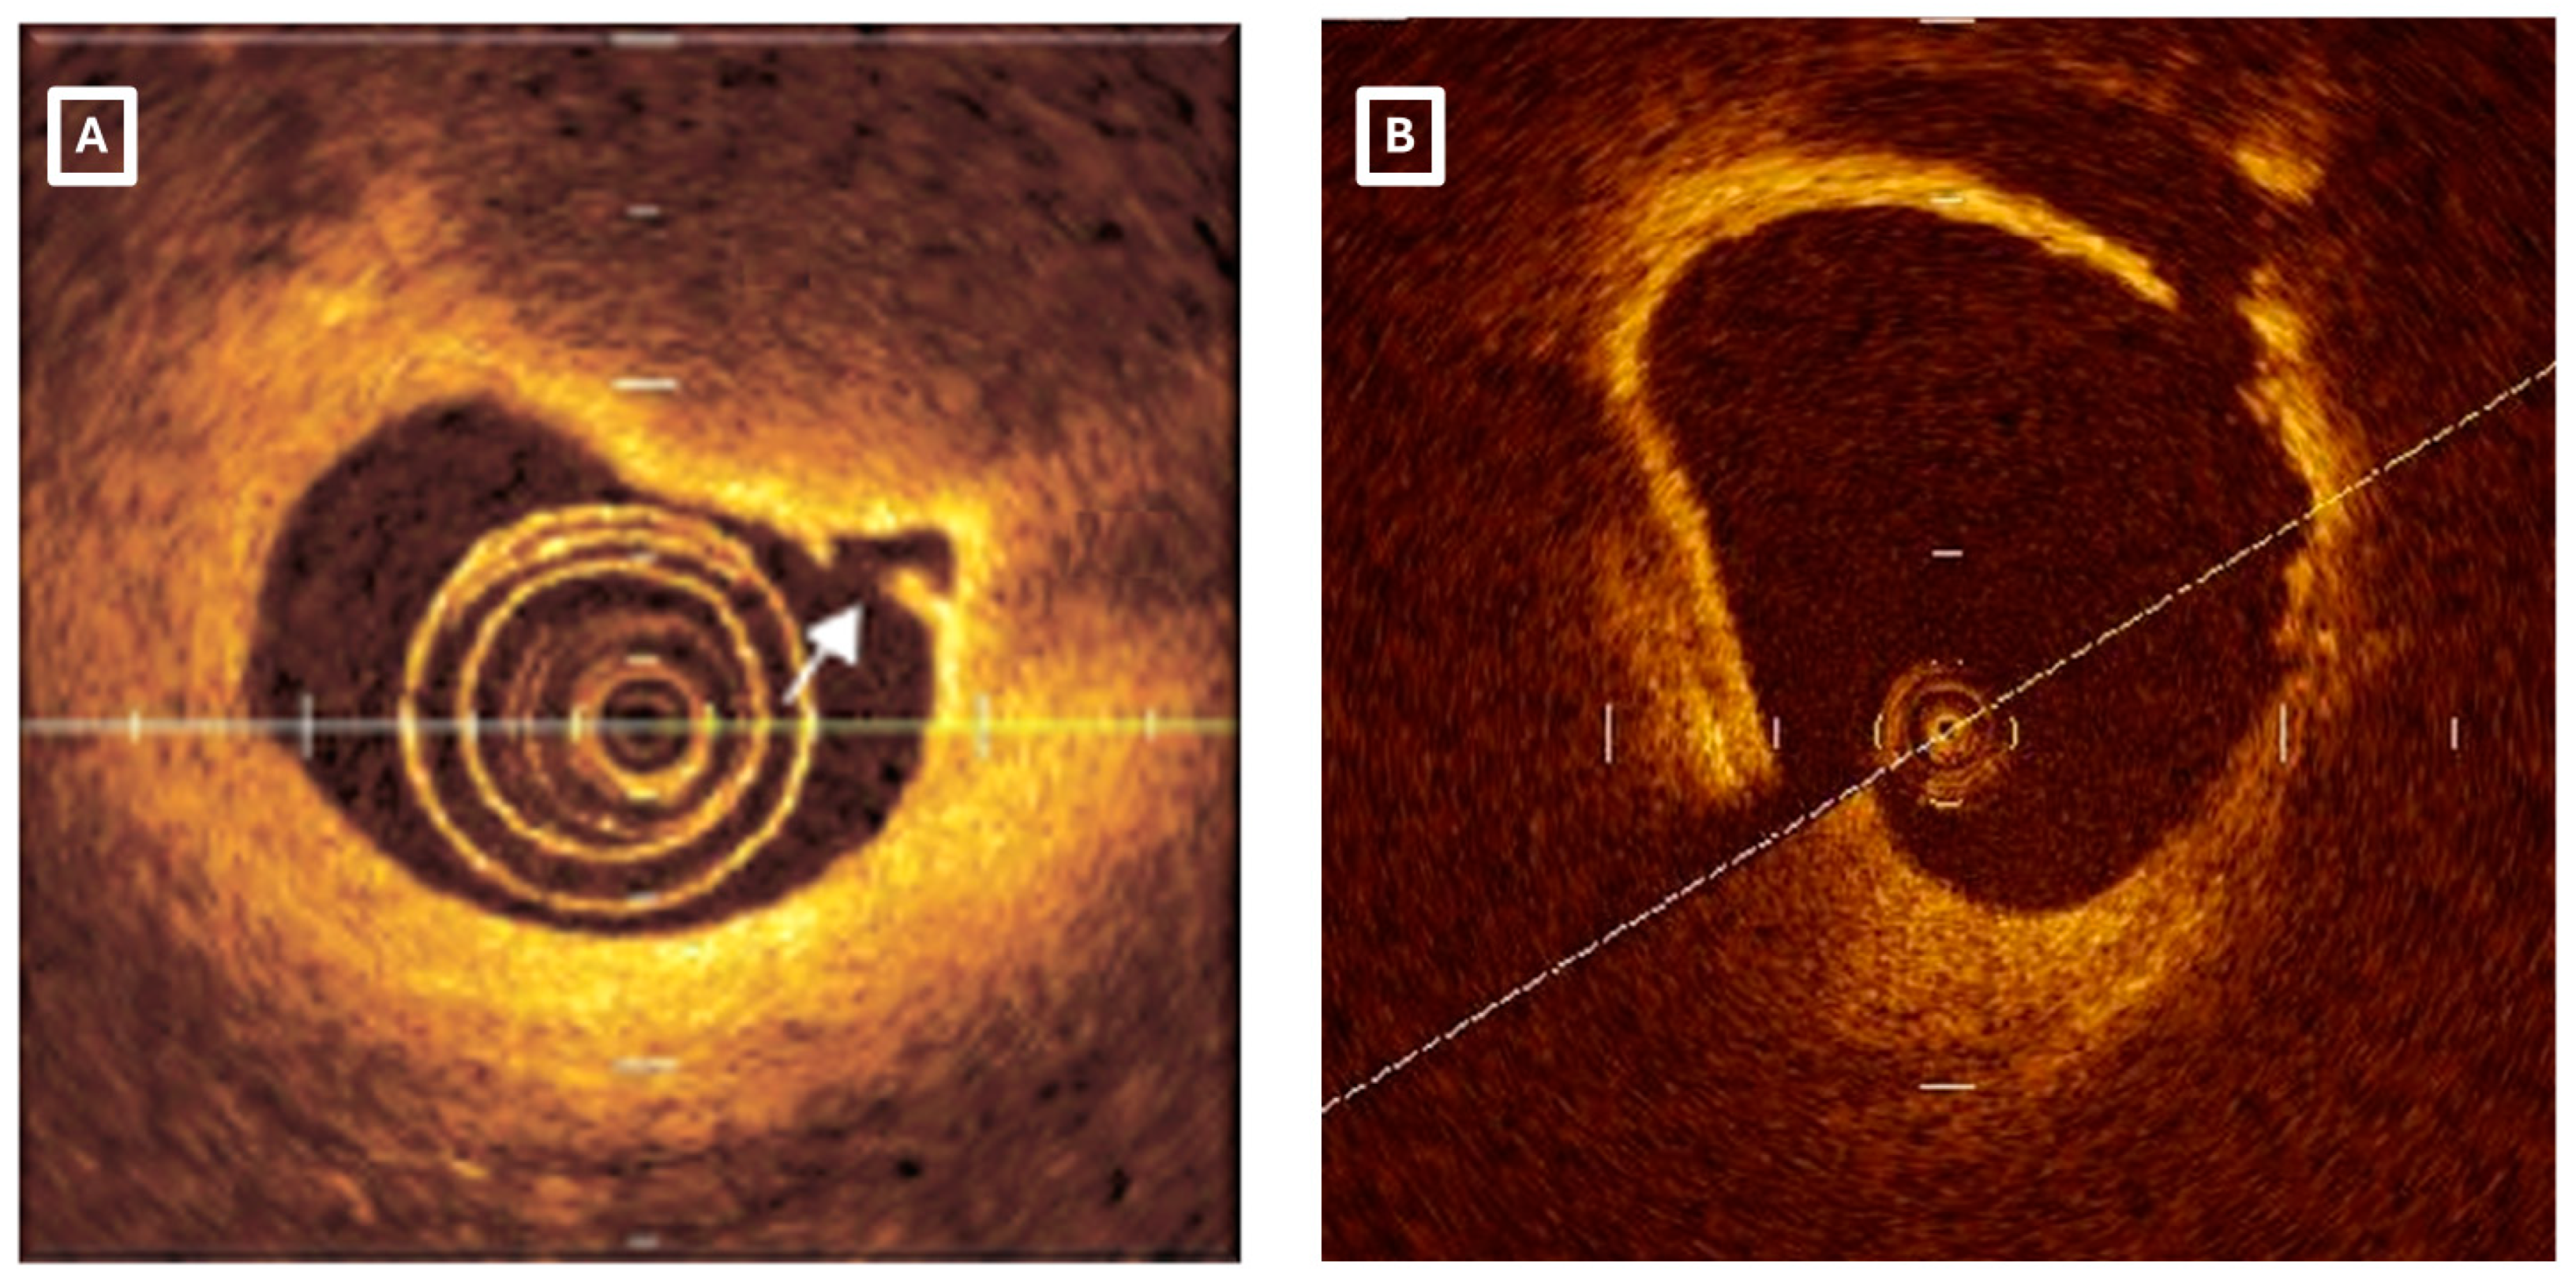

- Cuesta, J.; Antuna, P.; Jimenez, C.; Rivero, F.; Bastante, T.; Garcia-Guimaraes, M.; Alfonso, F. Can Plaque Erosion Be Visualized by High-Definition Intravascular Ultrasound? JACC Cardiovasc. Interv. 2020, 13, e57–e61. [Google Scholar] [CrossRef] [PubMed]

- Terada, K.; Kubo, T.; Kameyama, T.; Matsuo, Y.; Ino, Y.; Emori, H.; Higashioka, D.; Katayama, Y.; Khalifa, A.K.M.; Takahata, M.; et al. NIRS-IVUS for Differentiating Coronary Plaque Rupture, Erosion, and Calcified Nodule in Acute Myocardial Infarction. JACC Cardiovasc. Imaging 2021, 14, 1440–1450. [Google Scholar] [CrossRef] [PubMed]